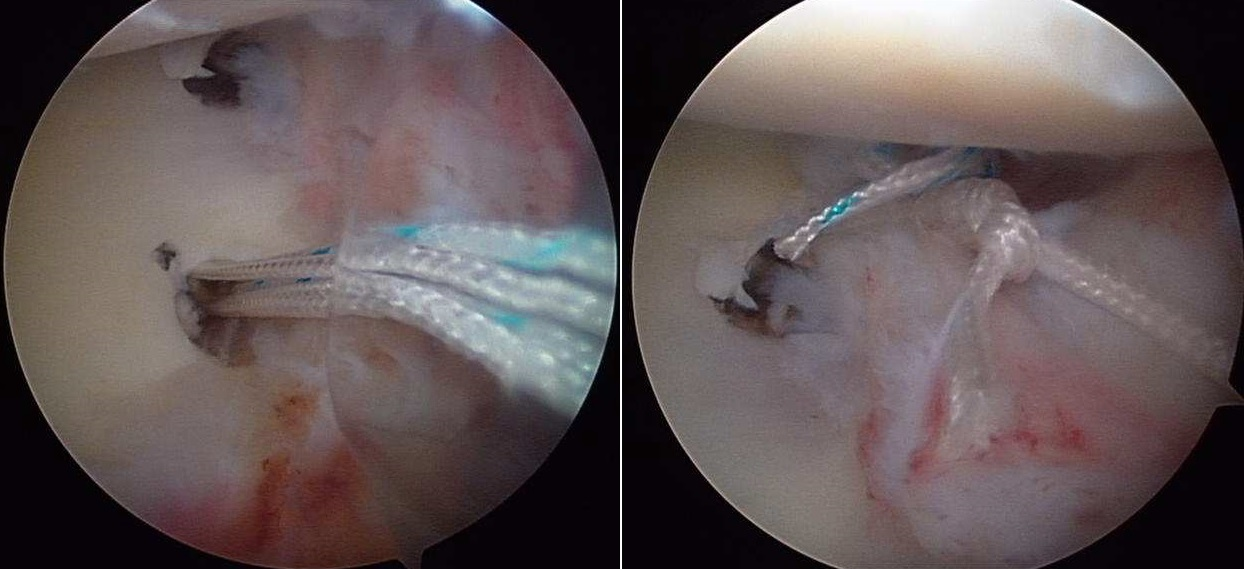

In the past 15 years improvements in arthroscopic techniques (small incisions to access the joint and small instruments controlled by microcameras) have greatly improved results. The advantage of not excising the muscles and the precision in repairing the tears makes this technique suitable for young patients (from 15 to 30 yrs of age), with a limited number of dislocations and with microinstablity. The technique uses “suture anchors” similar to microscrews (in titanium or resorbable polylactic acid) with nonresorbable highly resistant threads that are passed and tied to the joint capsule and to the glenoid labrum to recreate the normal capsular tension.

Arthroscopic capsuloplastic